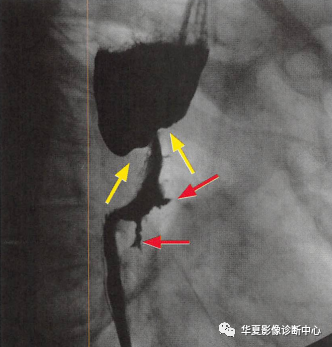

一定要小心食管的"黑色玫瑰花征"【YXZX093】

食管癌在鋇餐造影下的一種表現(xiàn)之一,顯示食管局部不規(guī)則狹窄(黃箭頭:玫瑰花花干),近端食管擴(kuò)張(萎陷的玫瑰花朵),兩個(gè)不規(guī)則線(xiàn)狀潰瘍(紅箭頭:玫瑰花葉/刺),形似黑色玫瑰花,小編原創(chuàng)命名為:“黑色玫瑰花征”,幫助記憶,加深映像